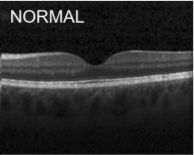

Eye diseases or ocular dysfunctions are fairly frequent in the general population, particularly among the elderly. The most significant anomalies in the eyes are choroidal neovascularization (CNV), diabetic macular edema (DME), and drusen accumulation in the macular region. In the recent decade, optical coherence tomography (OCT) has become one of the most rapidly evolving medical imaging technologies which can capture blood flow, polarization state, structural data, elastic properties, and molecular content, among other things, in biological tissues [1]. Optical diffraction and absorbance of biological tissues can be accurately measured with OCT and thus some diagnostic measures benefit from it.

Optical coherence tomography (OCT) images were selected from retrospective cohorts of adult patients from different hospitals around the world. OCT Images are labeled as (disease)-(randomized patient ID)-(image number by this patient) [11] and Fig 1 shows some examples of OCT images. Image properties are presented in Table II and the distribution of image quantity is presented in Table III. Custom image generators resize images to 224x224x3 and normalize them